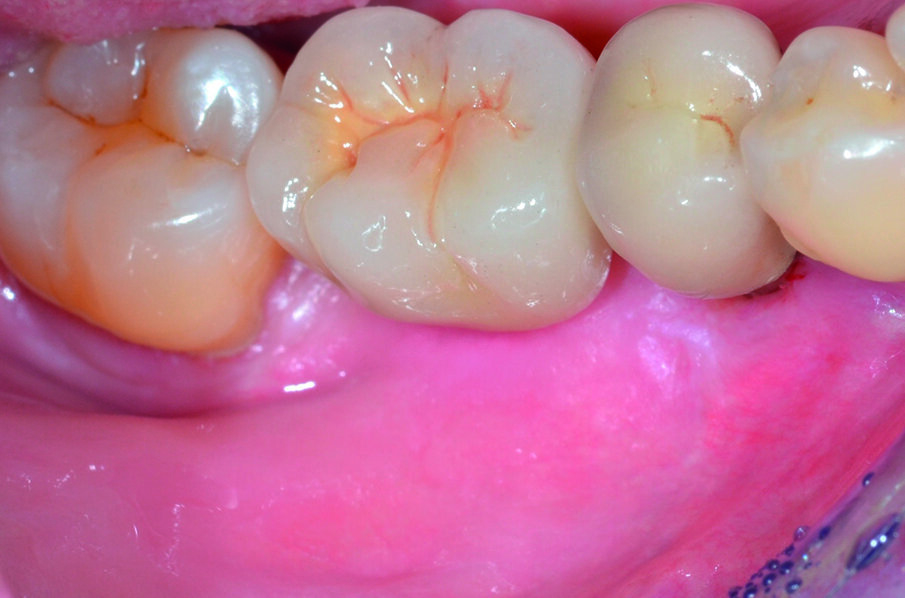

Paziente di aa. 62, femmina, giunge all’osservazione lamentando mobilità dell’elemento 4.5, dolorabilità e sanguinamento evocato durante le manovre di igiene orale (Fig. 1). Al sondaggio parodontale e all’esame radiografico endorale si evidenzia una consistente infiammazione del parodonto marginale associata a un vasto difetto intraosseo di tipo circonferenziale che interessa la superficie radicolare distale e buccale dell’elemento in oggetto (Figg. 2, 3). Al termine della terapia causale e della terapia parodontale non chirurgica il paziente è sottoposto a successiva rivalutazione, in base alla quale viene programmata una procedura di Rigenerazione Tissutale Guidata (G.T.R.) sull’elemento 4.5 associata ad inserimento di un impianto osteointegrato in sede 4.6. Poiché l’elemento dentario interessato dal difetto è adiacente ad uno spazio edentulo, la tecnica chirurgica di scelta è quella denominata “Crestal Incision”.